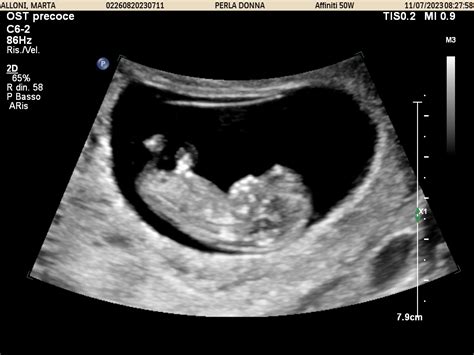

L’ecografia ostetrica rappresenta uno strumento imprescindibile per il monitoraggio dello sviluppo fetale e la valutazione del benessere in utero. Eseguita entro il termine del primo trimestre, questa indagine ha il compito di indagare il numero di feti, la loro vitalità e l'epoca gestazionale. In questa prima fase, infatti, la lunghezza cranio-caudale (CRL), ovvero la lunghezza vertice-sacro, appare pressoché costante in feti di identica datazione. Pertanto, rilevando questo parametro tramite immagini ecografiche, il medico può stabilire l'età gestazionale e la data presunta del parto, il tutto con un ottimo grado di approssimazione. Se misurata tra la 7a e la 11a settimana, ad esempio, la lunghezza cranio-caudale (CRL) ha un'accuratezza di più o meno 3/4 giorni nel 95% dei casi.

Nella gravidanza iniziale, il clinico si avvale di tabelle di riferimento che riportano le misure medie di frequenza cardiaca (Embryonic Heart Rate), il diametro del sacco gestazionale (GSD) e il diametro del sacco vitellino (YSD) in relazione alle dimensioni dell’embrione. Parallelamente, il diametro biparietale (BPD), quando misurato tra la 12a e la 16a settimana, offre un'accuratezza analoga alla lunghezza cranio-caudale, garantendo un margine di errore di più o meno 3/4 giorni nel 95% dei casi. Un punto di riferimento essenziale per l'analisi del BPD nel primo trimestre è il lavoro del gruppo di Yves Ville, pubblicato nel 2003, che fornisce un grafico preciso dell'andamento di tale parametro.

A partire dalla 14a settimana, la complessità dell'indagine aumenta poiché esistono parametri specifici per le varie parti del corpo. Per gli operatori del settore, il riferimento principale rimane lo studio di Snijders e Nicolaides del 1994, un testo estremamente tecnico che definisce gli standard biometrici per la seconda fase della gravidanza. Dopo il primo trimestre, aumentano significativamente le possibilità di riconoscere patologie malformative del feto. È in questo contesto che, intorno alla ventesima settimana, si esegue l'ecografia morfologica, finalizzata a valutare una serie di parametri biometrici cruciali.

In questa fase, l'attenzione del medico si focalizza su segnali che potrebbero indicare anomalie cromosomiche. Ad esempio, la riduzione della lunghezza dell'omero o del femore rispetto ai valori di riferimento si osserva frequentemente nella trisomia 21 (sindrome di Down). La misura del BPD, della lunghezza del femore, della circonferenza cranica e di quella addominale (CA) è inoltre fondamentale per stabilire o confermare l'età gestazionale del piccolo.

Nel terzo trimestre (tra la 28a e la 32a settimana), l'ecografia ostetrica o biometrica indaga nuovamente la crescita e l'anatomia fetale, permettendo di rilevare eventuali malformazioni sfuggite alla precedente ecografia morfologica. È importante sottolineare che questa indagine ecografica non viene mai utilizzata per datare la gravidanza, parametro che dev'essere già stato chiaramente stabilito nelle precedenti ecografie. Piuttosto, l'ecografia biometrica valuta l'adeguatezza della crescita fetale in base a valori standard riferiti all'età gestazionale precedentemente stimata, monitorando costantemente il BPD, la lunghezza del femore (LF), la circonferenza cranica (CC) e quella addominale (CA).